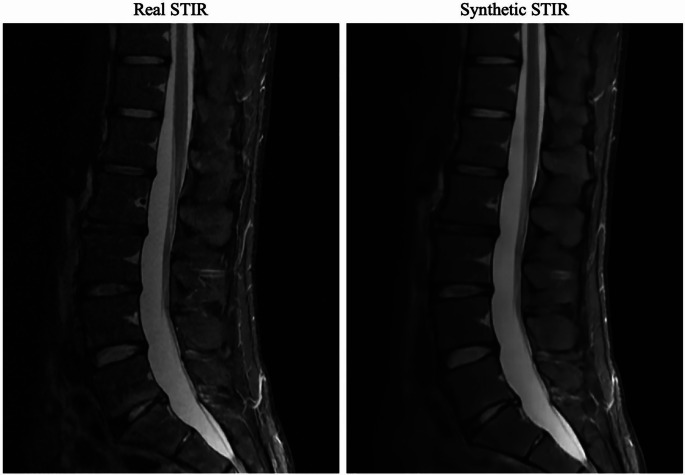

Recent findings: AI models have shown strong accuracy in preoperative planning, with neural networks outperforming traditional algorithms in patient selection and outcome prediction. Advances in 3D modeling, supported by machine learning, enable efficient, patient-specific anatomical reconstructions, reducing manual segmentation time from hours to seconds. In intraoperative navigation, AI-driven virtual and augmented reality systems enhance screw placement precision and reduce radiation exposure by up to 90%, improving workflow and safety. Additionally, real-time AI-based decision support has decreased operative time and postoperative risks, while postoperative AI applications now support mortality risk stratification and discharge planning, yielding significant predictive accuracy for adverse events and extended stays. AI technologies are transforming spine surgery by increasing surgical precision, optimizing clinical workflows, and personalizing patient care. While challenges remain regarding data diversity and ethical considerations, ongoing innovations indicate that AI will continue to refine spine surgery through personalized and efficient care solutions.